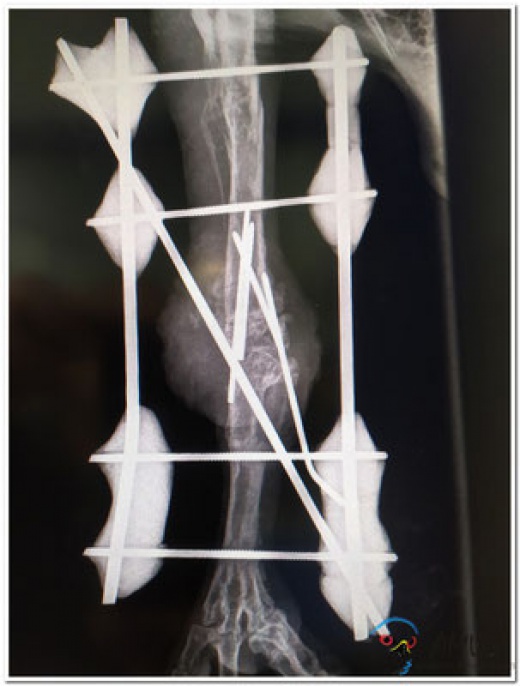

En mai 2017, l’oiseau avait été accueilli dans le centre spécialisé de Vallcalent (Espagne) avec une luxation sévère du tibia-tarse dont la cause était inconnue. En effet, le jeune rapace issu du couple reproducteur sauvage de l’Aude boitait gravement de la patte gauche, il a donc été retiré de son nid. Les premiers soins ont été mis en place avec un traitement conservateur par bandage pour tenter de remettre la patte dans une bonne position anatomique. En septembre 2018, après une période d’adaptation à sa nouvelle condition, l’oiseau a été opéré et s’est bien rétabli mais cela n’a pas suffi.

Il a donc été décidé d’opérer de nouveau le rapace en décembre 2019. Cette opération devait lui permettre d’enfin se déplacer correctement et de faire de lui un reproducteur dans le centre d’élevage spécialisé de Valcallent pour contribuer à la conservation de l’espèce.

L’opération a été un succès et un mois après, les premières nouvelles sont encourageantes. Peu à peu, la patte du rapace guérit et il entame en ce moment le deuxième cycle d’antibiotique tout en alternant physiothérapie et chaussures orthopédiques afin de retrouver la motricité de sa patte.